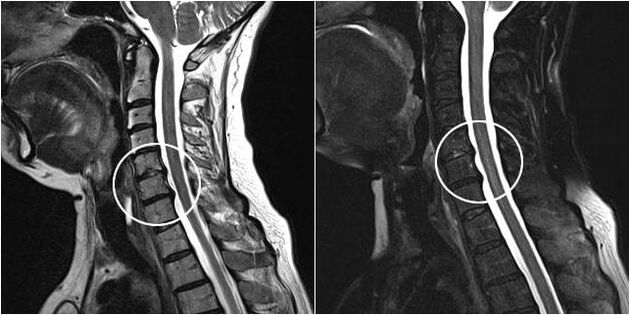

As the intervertebral discs and vertebrae deform, the patient's condition worsens.The course of osteochondrosis is complicated by neurogenic symptoms caused by compression by osteophytes or hernial protrusion of the spinal roots and vertebral artery.Headaches, dizziness, changes in blood pressure appear, and visual and auditory acuity decreases.

Indications for surgical intervention include the ineffectiveness of conservative treatment, as well as complications of cervical osteochondrosis, for example, discogenic myelopathy, vertebral artery syndrome and radicular syndrome.To decompress the spinal cord, blood vessels and spinal roots, the following operations are performed:

During surgery, fragments of bone and ligaments may be removed, and intervertebral discs may be completely or partially removed.For small hernial protrusions, laser vaporization of the disc nucleus is often performed.